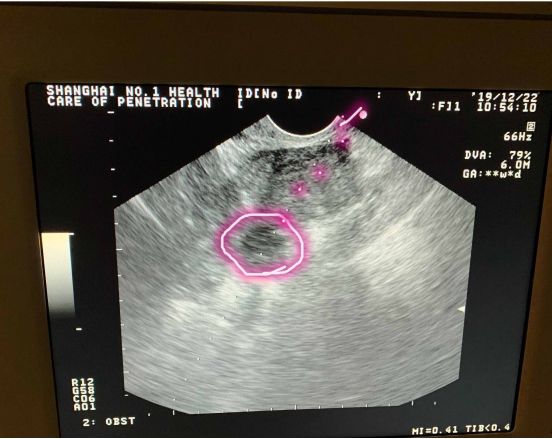

其实现在的取卵手术比较简单,就是在阴道超声的监护下,用一根细细长长的取卵针扎入卵泡中,通过负压吸引将卵子取出体外的技术。

如果卵巢位置好,患者心理放松、对医生充分信任,再加上医生取卵技巧娴熟,那取卵过程会完全不痛或仅有轻微的痛感;反之,如果卵巢位置不好,在子宫后方,取卵针穿过子宫后才能穿刺到卵泡,那必定会有疼痛感的。

像这种情况,穿刺针进去就是卵泡,还没来得及疼呢手术就结束了!

而这种情况,取卵针要经过子宫,长途跋涉后才能刺入卵泡,那肯定疼,我给你取卵也会疼!